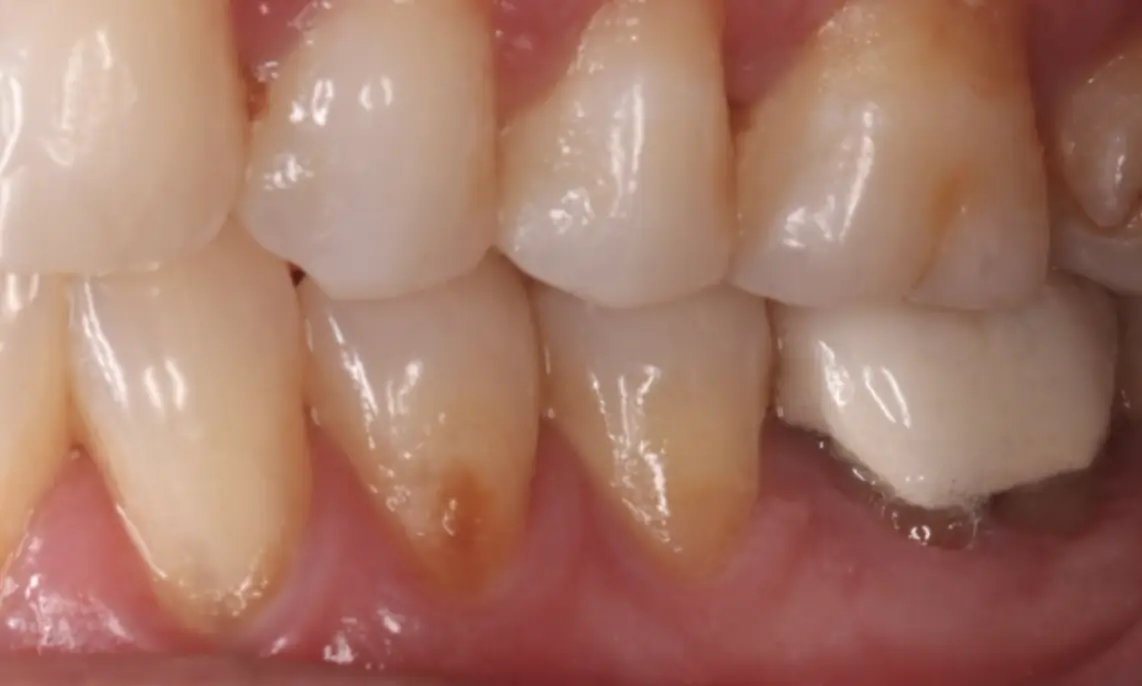

Connective Tissue Graft

before

after